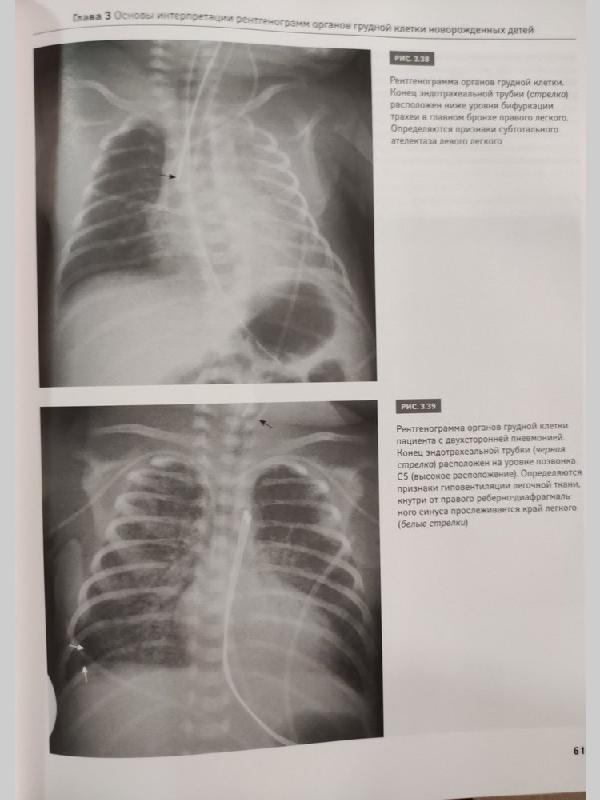

Рентгенодиагностика заболеваний легких у новорожденных детей: монография / М.В. Дегтярева, А.В. Горбунов, А.П. Мазаев, А.В. Ерохина. - М.: Логосфера, 2017. - 200 с. ISBN 978-5-98657-059-4 В монографии изложены основные подходы к рентгенодиагностике заболеваний легких у новорожденных детей, представлены развитие и нормальная анатомия легких, методика рентгенологического исследования, разобраны особенности интерпретации рентгеновских изображений грудной клетки и рентгеносемиотика заболеваний легких у самых маленьких пациентов. Книга содержит более 200 иллюстраций - рисунков и рентгенограмм органов грудной клетки и брюшной полости. Описаны сложные случаи диагностики и дифференциальной диагностики как редких пороков развития, так и часто встречающихся патологических состояний дыхательной системы новорожденных детей. Книга дополнена DVD с файлами рентгенограмм (цифровых и аналоговых), приведенных в книге. Данное издание предназначено для рентгенологов, неонатологов, педиатров, анестезиологов-реаниматологов, врачей скорой помощи, студентов медицинских вузов и других специалистов, работающих в смежных областях.